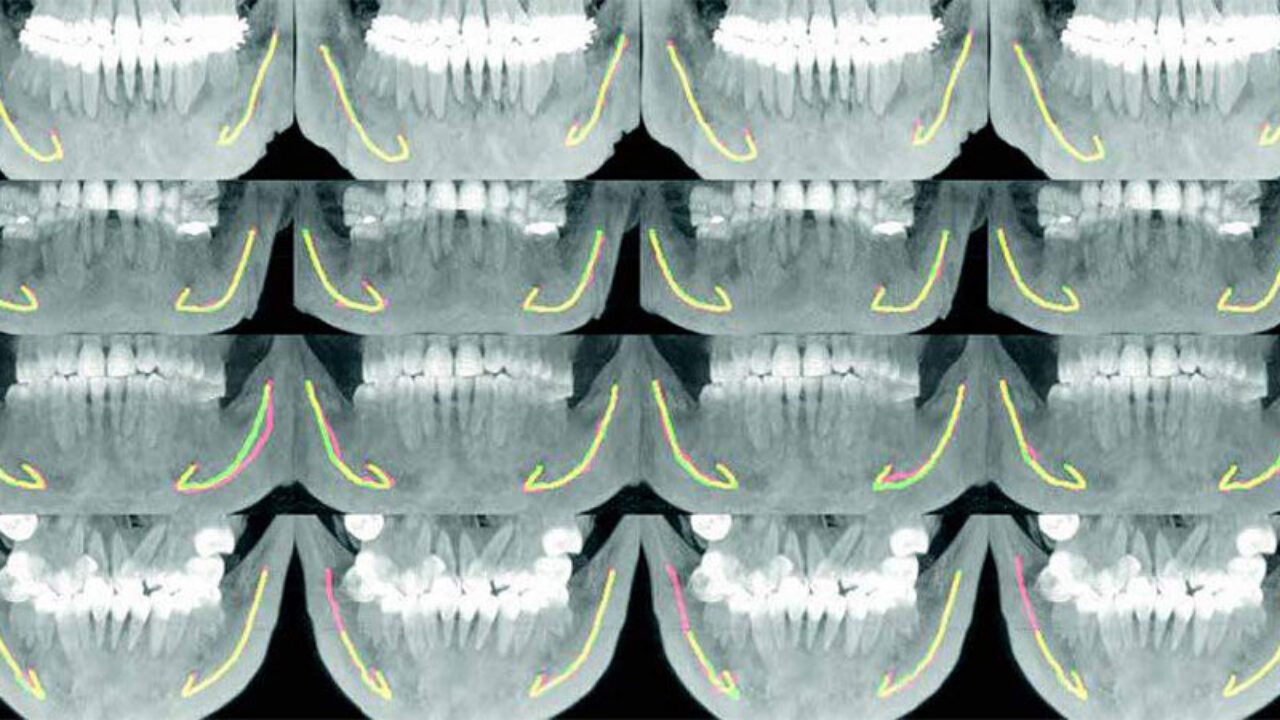

Εικ.2 Εικόνες CBCT που δείχνουν επικαλυπτόμενες τμηματοποιή- σεις συστημάτων ειδικών και βαθιάς μάθησης. Κάθε εικόνα σε κάθε στήλη σχολιάζεται από τον ίδιο ειδικό, εμφανίζεται με κόκκινο, ο σχολιασμός του συστήματος βαθιάς εκμάθησης εμφανίζεται με πράσινο και η επικάλυψη εμφανίζεται με κίτρινο.